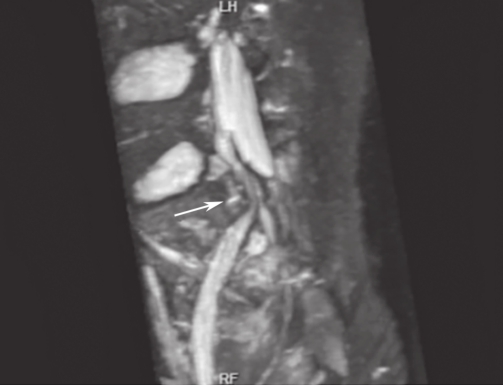

白靖平等认为用MRI扫描骶骨斜冠状面,当有骶神经损伤时,MRI图像显示骶神经周围脂肪组织消失,其直径变窄,且神经走向改变等。许道洲等则认为MRI平扫不能直接显示骶神经根的损伤,MRI SPACE-STIR序列扫描能提供三维TSE对比成像。在SPACE-STIR序列扫描图像上,在骨折周围出现下列征象时应考虑有神经根的损伤:①神经节后线状高信号走行中断,是诊断神经根损伤的直接征象,表现为神经根在骨折处呈截断征,如图2-15;②神经根走行发生改变,是诊断神经根损伤可靠的间接征象,表现为神经根自然走行弧度消失,在骨折处呈弧形受压移位改变,甚至出现成角改变,如图2-16;③神经异常肿胀增粗,是诊断神经根损伤的间接征象,表现为骨折附近神经明显较近端及远端增粗,如图2-17。

图2-15 斜冠状面SPACE-STIR序列MRI神经成像重建

可见右侧S

1

神经中断(箭头所指),对侧显示良好。